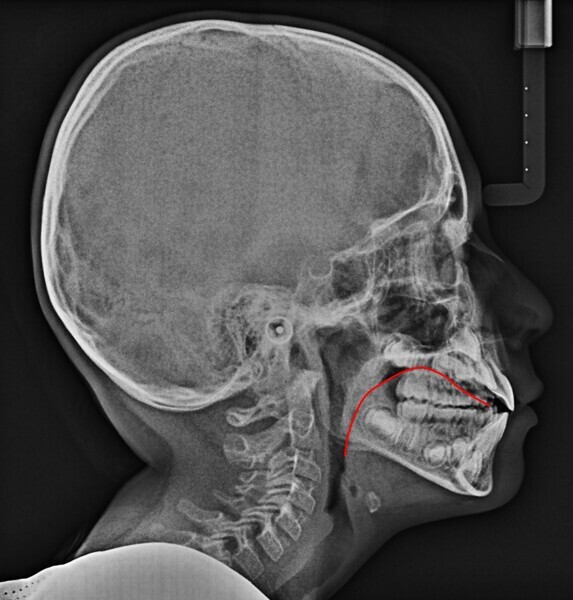

In my clinical practice, I prevent patients from rolling and rotating their heads using a cephalostat while allowing pitching: only after they have positioned themselves comfortably, do I place the post on the nasion, without exerting pressure. In this way, the patient will assume his or her habitual posture, and this too will be investigated by us. The cephalometric radiograph showed very important dysfunctional aspects (Fig. 4). Antero-rotation of the head and cervical hyper-lordosis were evident. Tracing of the tongue23 showed a very low position of the anterior part, as was found clinically. Cephalometric analysis was performed using the OrisCeph Rx1 CE program (Version 7.70; Elite Computer Italia). The patient showed a Class I skeletal pattern with antero-rotation of the maxillary plane, proclination of the mandibular incisors and increased anterior lower face height.

In the control cephalometric radiograph, the lingual position had completely regularised, the body and tip being in contact with the hard palate, creating an average overbite (Fig. 14). The cervical hyper-lordosis was moving towards correction and the skull posture was less forward.

Functional cephalometric analysis showed clear improvements too (Fig. 15; Table 1). The maxillary plane, which indicates the orientation of the maxilla, had undergone regularisation in both the angle with the skull base (SN line; going from a value of 7.7° at T0 to one of 11.2° at T1) and the angle with the Frankfort plane (going from a value of −2.9° at T0 to one of 0° at T1). The inter-incisal angle had increased, indicating an improvement in the inter-incisal ratios. The excessively divergent angle between the maxillary plane and the mandibular plane had decreased, and the facial divergence regarding both the mandibular angle and the face height index showed remarkable normalisation. Of note, was the reduction in proclination of the mandibular incisors, which went from a mandibular incisor to mandibular plane angle of 96.8° to one of 92.1°.

In agreement with Yoon et al.,4 in the radiographs at T0 and T1, we also calculated the length of the soft palate because its increase in size, as far as we know, is considered a risk factor for the development of obstructive sleep apnoea, and its reduction is part of the therapeutic goals of myofunctional therapy for the treatment of obstructive sleep apnoea.28, 29 The P–PNS value had decreased from T0 (30.0 mm) to T1 (29.4 mm). Also in agreement with Yoon et al.,4 we also calculated the length of the perpendicular from the hyoid bone to the mandibular plane. An increase indicates a low tongue posture. This line had fallen from T0 (16.3 mm) to T1 (11.9 mm), giving further confirmation of improved lingual posture.

Comparison of the cephalometric radiographs, with evidence of the new lingual posture (Fig. 16), indicated a balance between the orofacial forces30 that allowed a new growth pattern that was less vertical than the previous one. Long-term follow-up of the patient will tell us whether this pattern will be maintained.